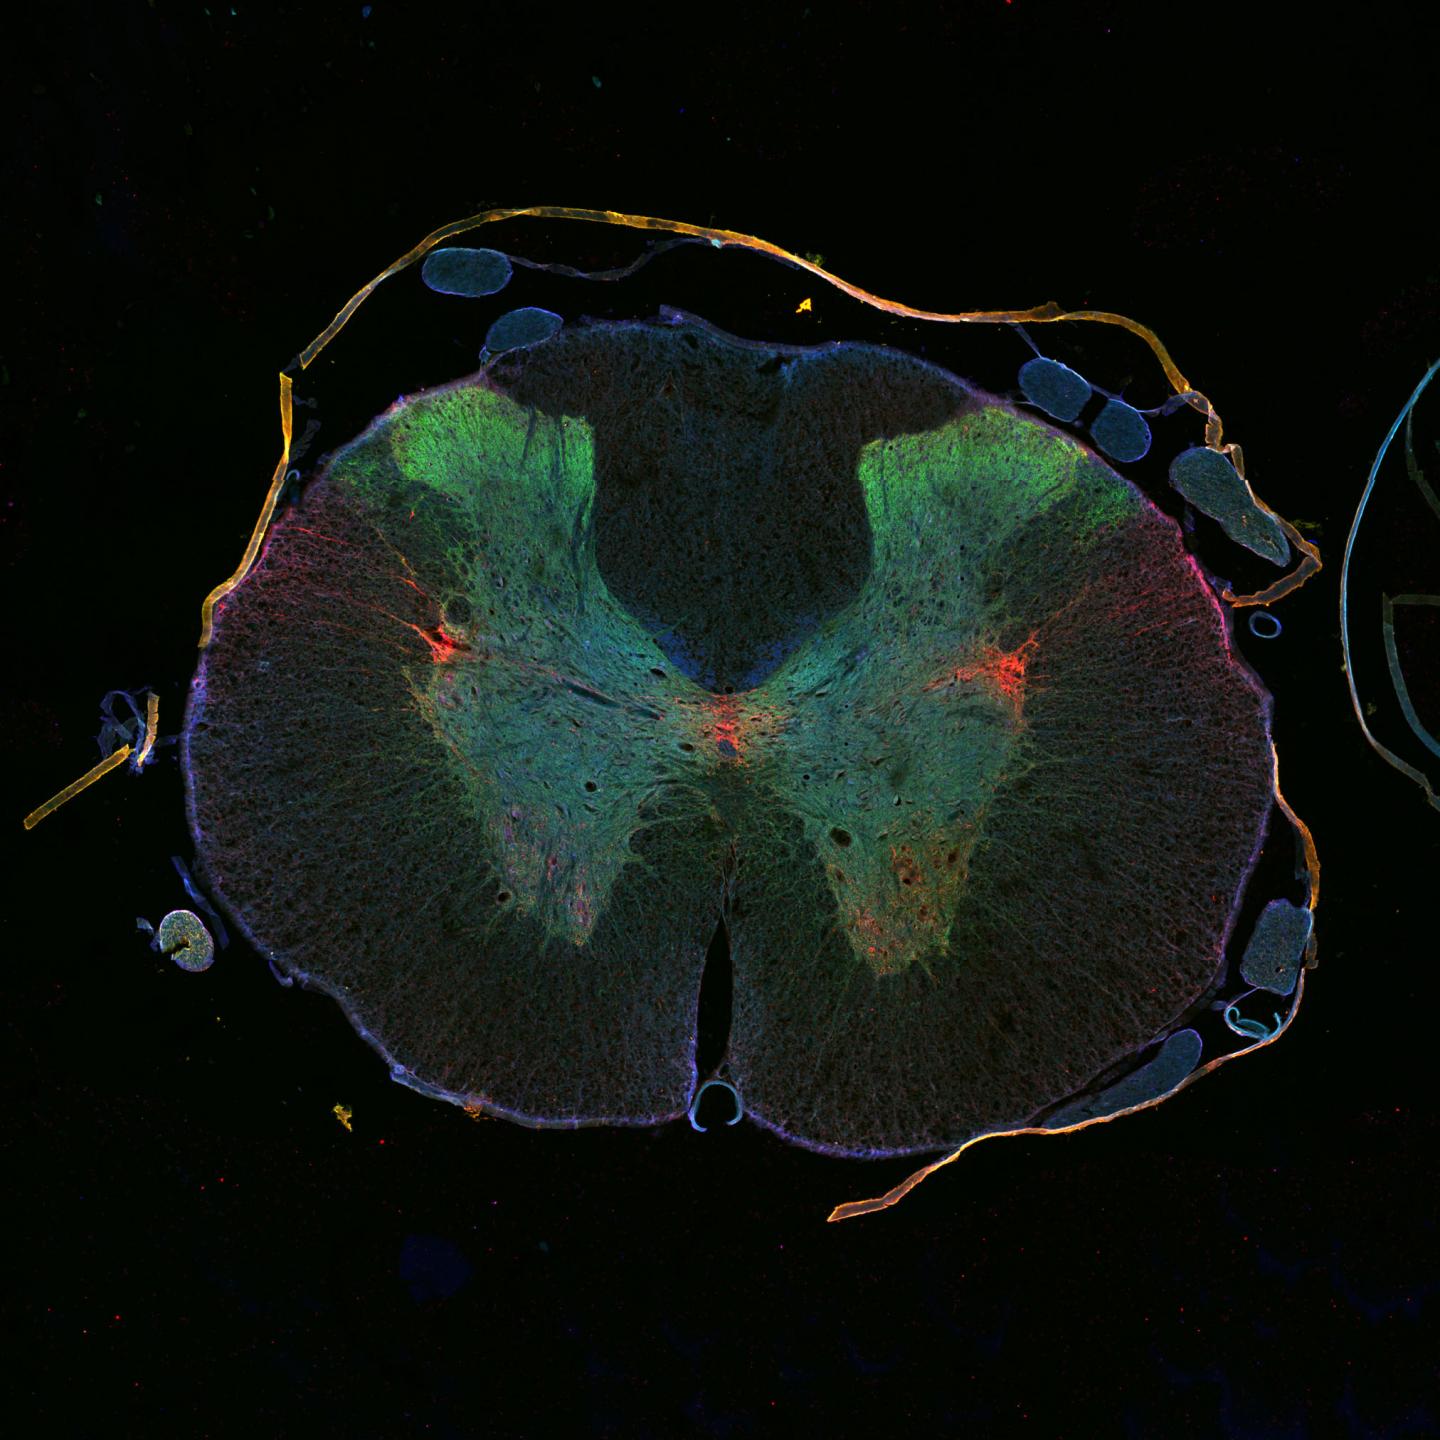

White Matter & Grey Matter. The spinal cord is split into grey matter (which is in the shape of a butterfly) and white matter (which is the material surrounding the grey). The white matter is made up of nerve fibers, called axons, which run up and down the length of the cord. Each group of axons carries a specific type of information it needs ...

Structure Of Spinal Cord. The Spinal cord runs through a hollow case from the skull enclosed within the vertebral column. Spinal nerves arise from different regions of the vertebral column and are named accordingly, the regions are – Neck, chest, pelvic and abdominal. Cross-section of spinal cord displays grey matter shaped like a butterfly ...